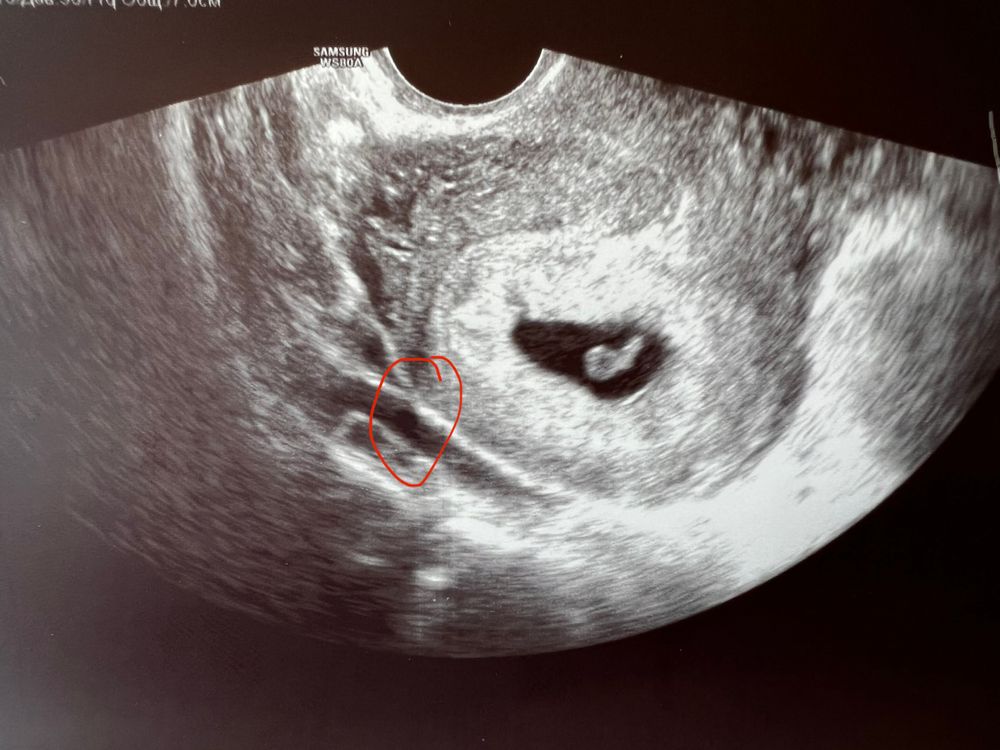

Плохое плодное яйцо